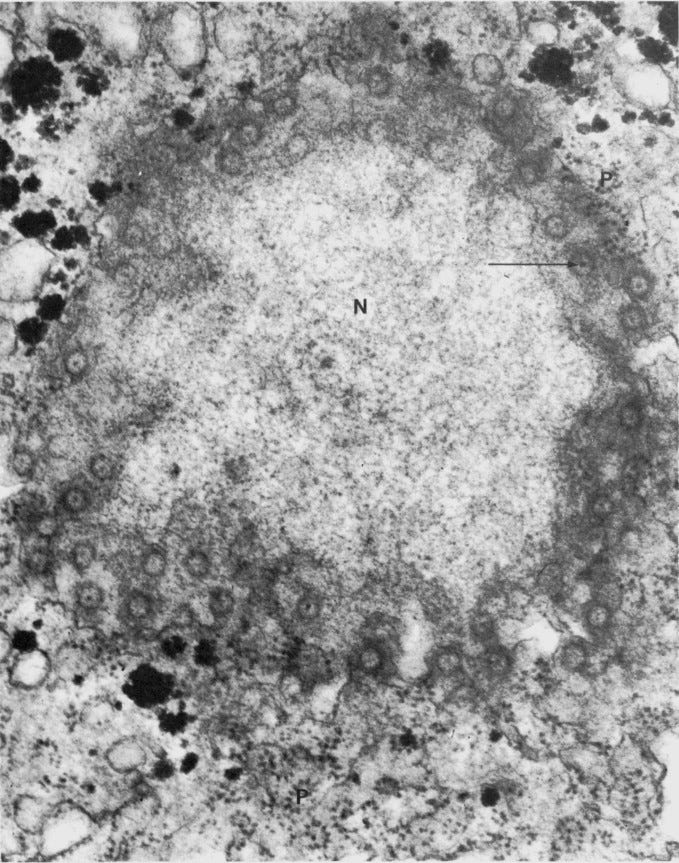

Figure 1A illustrates the accumulation of 3.2-nm-sized thioglycolic acid (TGA)-capped QDs in the nucleus and nucleoli of THP1 cells after 30 minutes of incubation.

The fluorescence pattern indicates predominant membrane-associated fluorescence and discrete cytoplasmic aggregates of cysteamine-capped CdTe QDs (positively charged) following the same incubation period, as shown in Figure 1B.

However, no nuclear or nucleoli accumulation is observed with the positively charged QDs.

Experiments with cysteamine-capped QDs rule out particle size as the reason for the differing ultimate locations within the THP1 cells. This means surface charge of the QDs determine the cellular uptake mechanism and their ultimate location within the cell.

The size was not making things change where it went—it was the negative charge, as long as it was within the size to where it could get through a nuclear pore.